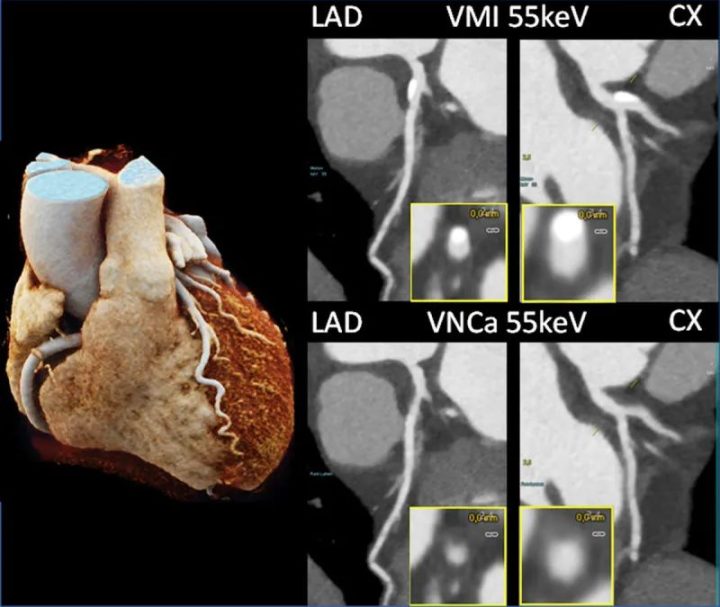

在一个相关的应用中,也是基于将物质分解为碘和钙,将钙化斑块从CTA成像的对比剂填充血管中去除,以提供虚拟非钙化图像(PURE Lumen,西门子医疗)。一项模型研究表明,在模拟心率高达每分钟80次的情况下,由严重钙化斑块引起的开花伪影减少,图像可解释性提高。因此,这种应用可以更好地评估血管管腔;不过,其功效还有待临床研究证实。图11显示了一个临床实例。

图11 用PCD-DSCT扫描的LAD和CX有钙化的患者的冠状动脉CTA图像(120 kV、144×0.4 mm、0.25 s旋转时间、66 ms时间分辨率)。55 keV虚拟单色成像(上)中显示的钙化在55 keV虚拟非钙化成像(下)中被去除。